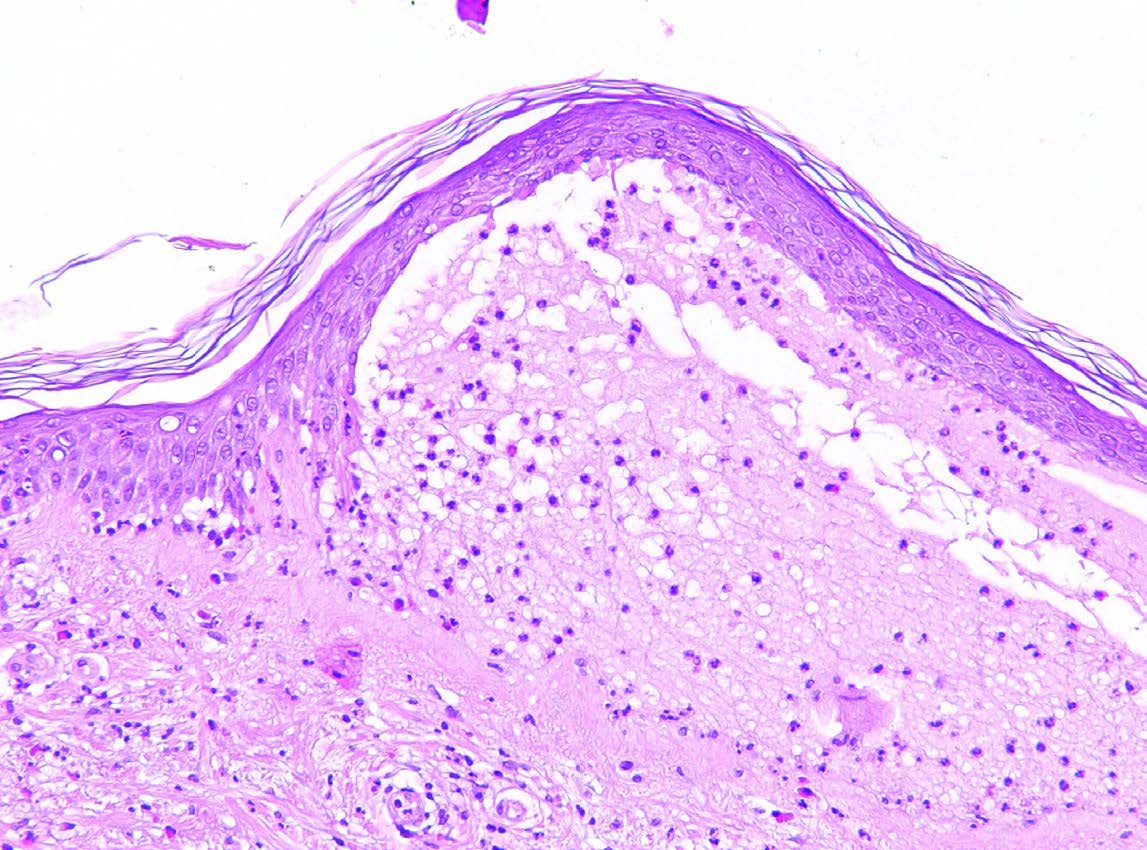

Bullous pemphigoid is an autoimmune condition causing sub-epidermal blistering of the skin. This is secondary to the development of antibodies against hemidesmosomal proteins BP180 and BP230.

Skin biopsy:

Histopathology of bullous pemphigoid. Lesional skin biopsy with subepidermal splitting and a dense inflammatory infiltrate of eosinophils and neutrophils in the upper dermis.